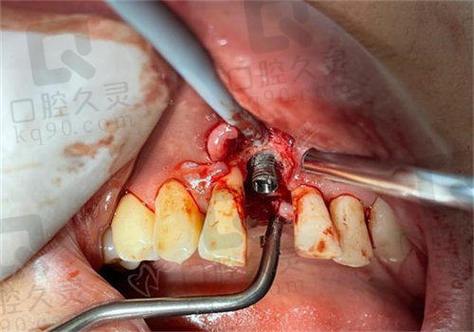

- 感染控制:若为种植体周围炎,需先进行清创(刮除感染组织)、冲洗,并全身或局部使用抗生素;若感染严重,需取出种植体,待炎症完全控制(通常2-4周)后再评估。

- 取出种植体:对于松动明显、骨吸收严重的种植体,需及时取出,避免残留种植体碎屑影响骨愈合,取出后彻底清理种植窝,去除炎性肉芽组织。